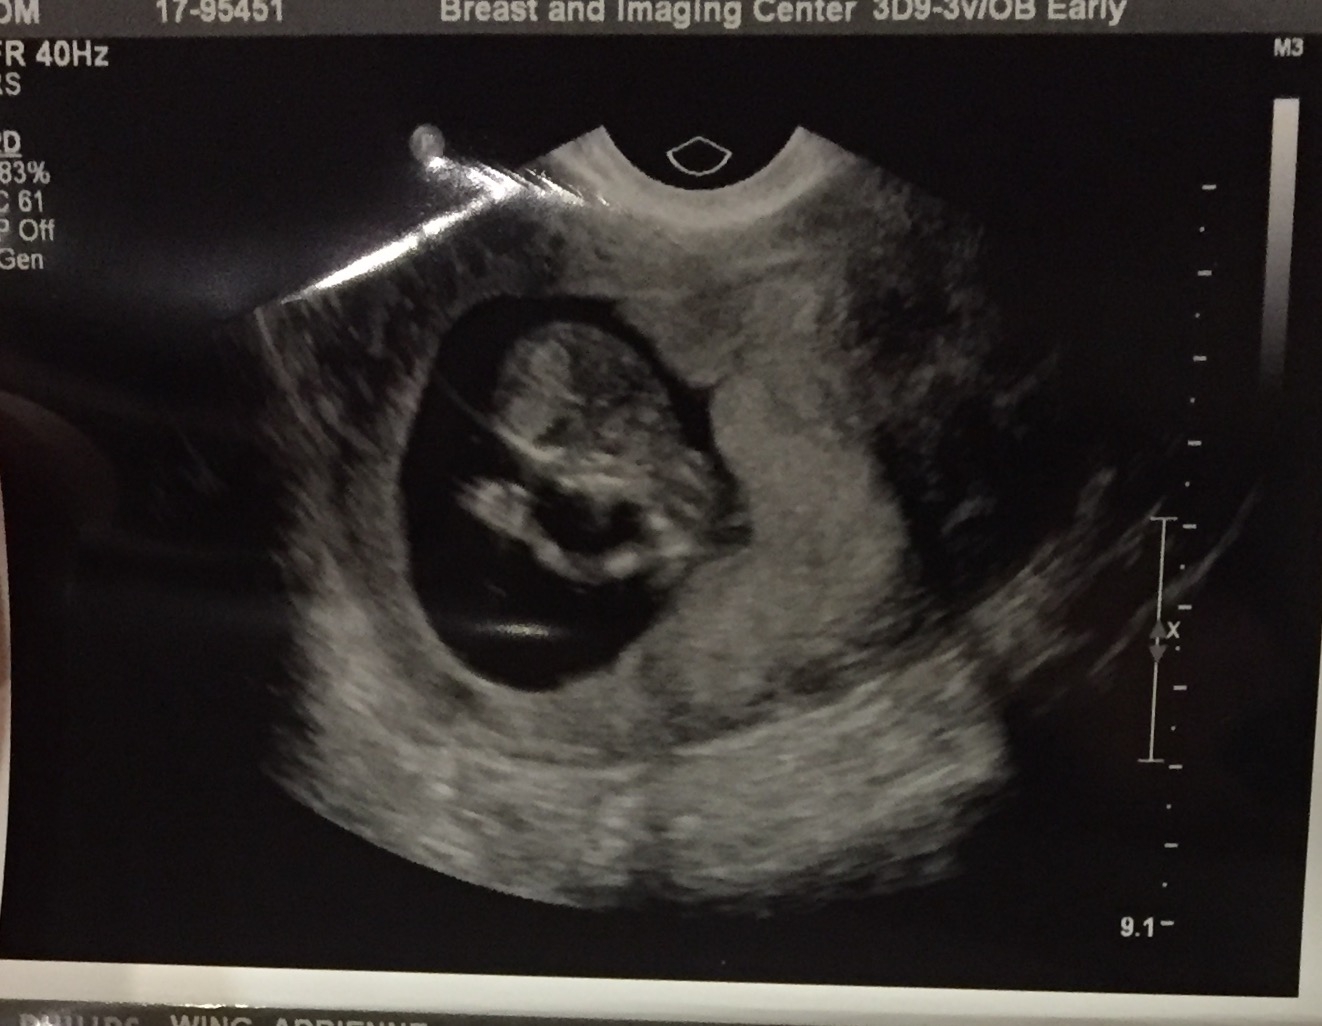

I couldn't log on through mobile, and literally fell asleep the moment I walked in the house. Baby girl is perfectly healthy and happy! We went to an imaging center today which has a much more detailed ultrasound done than the doctors office. It took 2 hours to get there, 4 hours there between waiting for the radiologist and then going to the OB afterwards, and then 2 hours back in rush hour traffic, so I was pooped! They also had some infrared scan and it was pretty neat to watch the movement through the placental cord to her. The blood was in fact a sub chorionic hemorrhage, like I thought(the OB was sure it wasn't last week). It is a bit large for size, and right next to placenta, so I need to go back in 2 weeks to check on it. The OB said more than likely it will reabsorb itself back into the uterus. I know they are so common, and i had a super tiny one at 6 weeks so I am not too worried. The OB of course let me know that there is a small risk of miscarriage with an SCH, which I know, but I am just pushing forward that everything is happy and healthy and will heal. They confirmed that I have 4 new fibroids compared from pre-IVF treatment, which means that all the hormone injections probably flared them up. They said more than likely they will not cause any issues for baby, but it will be uncomfortable for me, which I'm ok with as long as she is safe. All in all it was a great visit that has us full of relief!

ETA a pic of her waving at the camera. Look at those fingers!

@ChocolateIsLife so glad to hear that things are ok with baby and that the sch should be healing soon. Yay! ❤ and that's a great u/s pic of your girl! Keep that for the book!